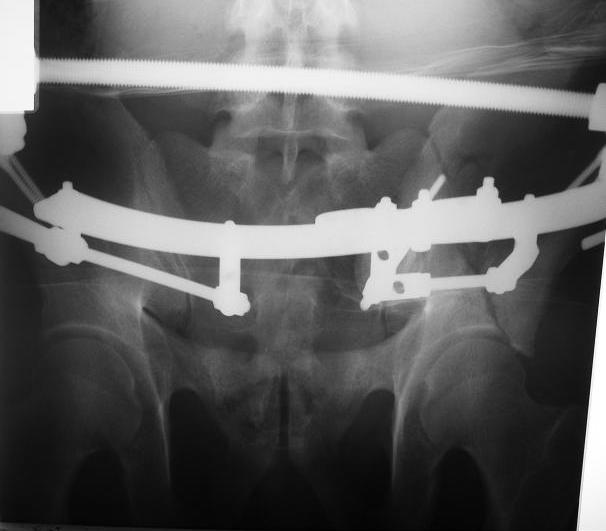

Поступил пациент после кататравмы (упал с высоты 4м). После обследования установлен Ds: Сочетанная травма. ЗТГК перелом 5-6 ребер справа. Ушиб левого леогкого. Оскольчатый перелом крыла подвздошной кости слева, со смещением. в экстренном порядке выполнена операция о/синтез таза стержневым аппаратом. Снимки прилагаются. Пациент со 2-го дня стал ходить без костылей. Из анамнеза жизни у пациента имеется гепатит В и С, с 1998г. употребляет наркотики (героин 1г в день нормальная доза). На контрольных снимках таза в аппарате смещение отломков сохраняется, да еще и стержни сломались. Подскажите ув.коллеги, как поступить в данной ситуации: оставить все как есть или добиваться репозиции в аппарате, или планировать на открытую репозицию. На сегодняшний день пациент стабилен, по анализам компенсирован. Принимает героин по другому справиться не может. С ув. Андрей

А сколько времени прошло после травмы? Аппарат лучше убрать: в таком виде он не выполняет никаких функций, а сломанные стержни скорее всего воспалятся и помешают доступу, если решите оперировать открыто. Целесообразно, как мне кажется сделать проекции Judet, чтоб определиться с линией перелома и возможным вовлечением вертлужной впадины. Вообще же лечение переломов крыла аппаратом - дело достаточно утомительное и часто неблагодарное - сложно управлять ротационным смещением и отведением/приведением фрагментов крыла, можно ухудшить стояние отломков.

Уважаемый Андрей, у пациента имеется перелом передней колонны,и после наложения аппарата положение отломков ухудшилось. возможно не из-за ваших действий а за счет тяги четырехглавой мышцы. Обе ости настойчиво будут тянуть крыло вниз.

C момента травмы прошло ровно 10 дней. Да Максим, вы как в воду глядели, у стержней появились признаки воспаления. Аппарат демонтирую.